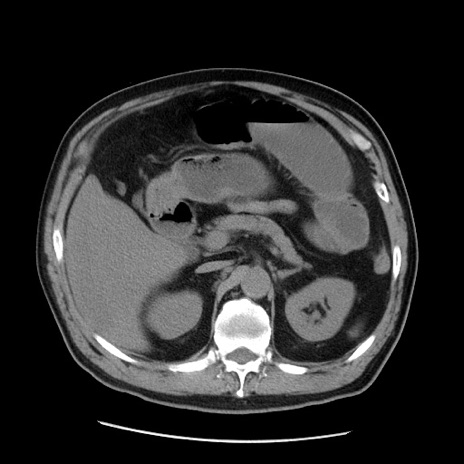

冠状断像

矢状断像

症例20(横断像)

【症例】 60歳代男性

【主訴】 腹部膨満、嘔吐

【現病歴】5日前頃より倦怠感を認め食事量減少し4日前の朝嘔吐、食事摂取困難となった。 3日前近医受診し点滴施行され整腸剤などを処方された。 当日他院を受診し、腹部膨満著明、炎症反応の上昇(CRP10.8、WBC11200)あり、紹介受診となる。

【身体所見】 意識JCS1 受け答えがはっきりしないBP 111/57mHg、 P 67bpm、、BT35.2°C、SpO2 97%(RA)、 腹部:膨隆、打診で鼓音あり、全体的に圧痛有り、腸蠕動音(-)、反跳痛ははっきりせず。

【データ】WBC 11400、CRP 14.20